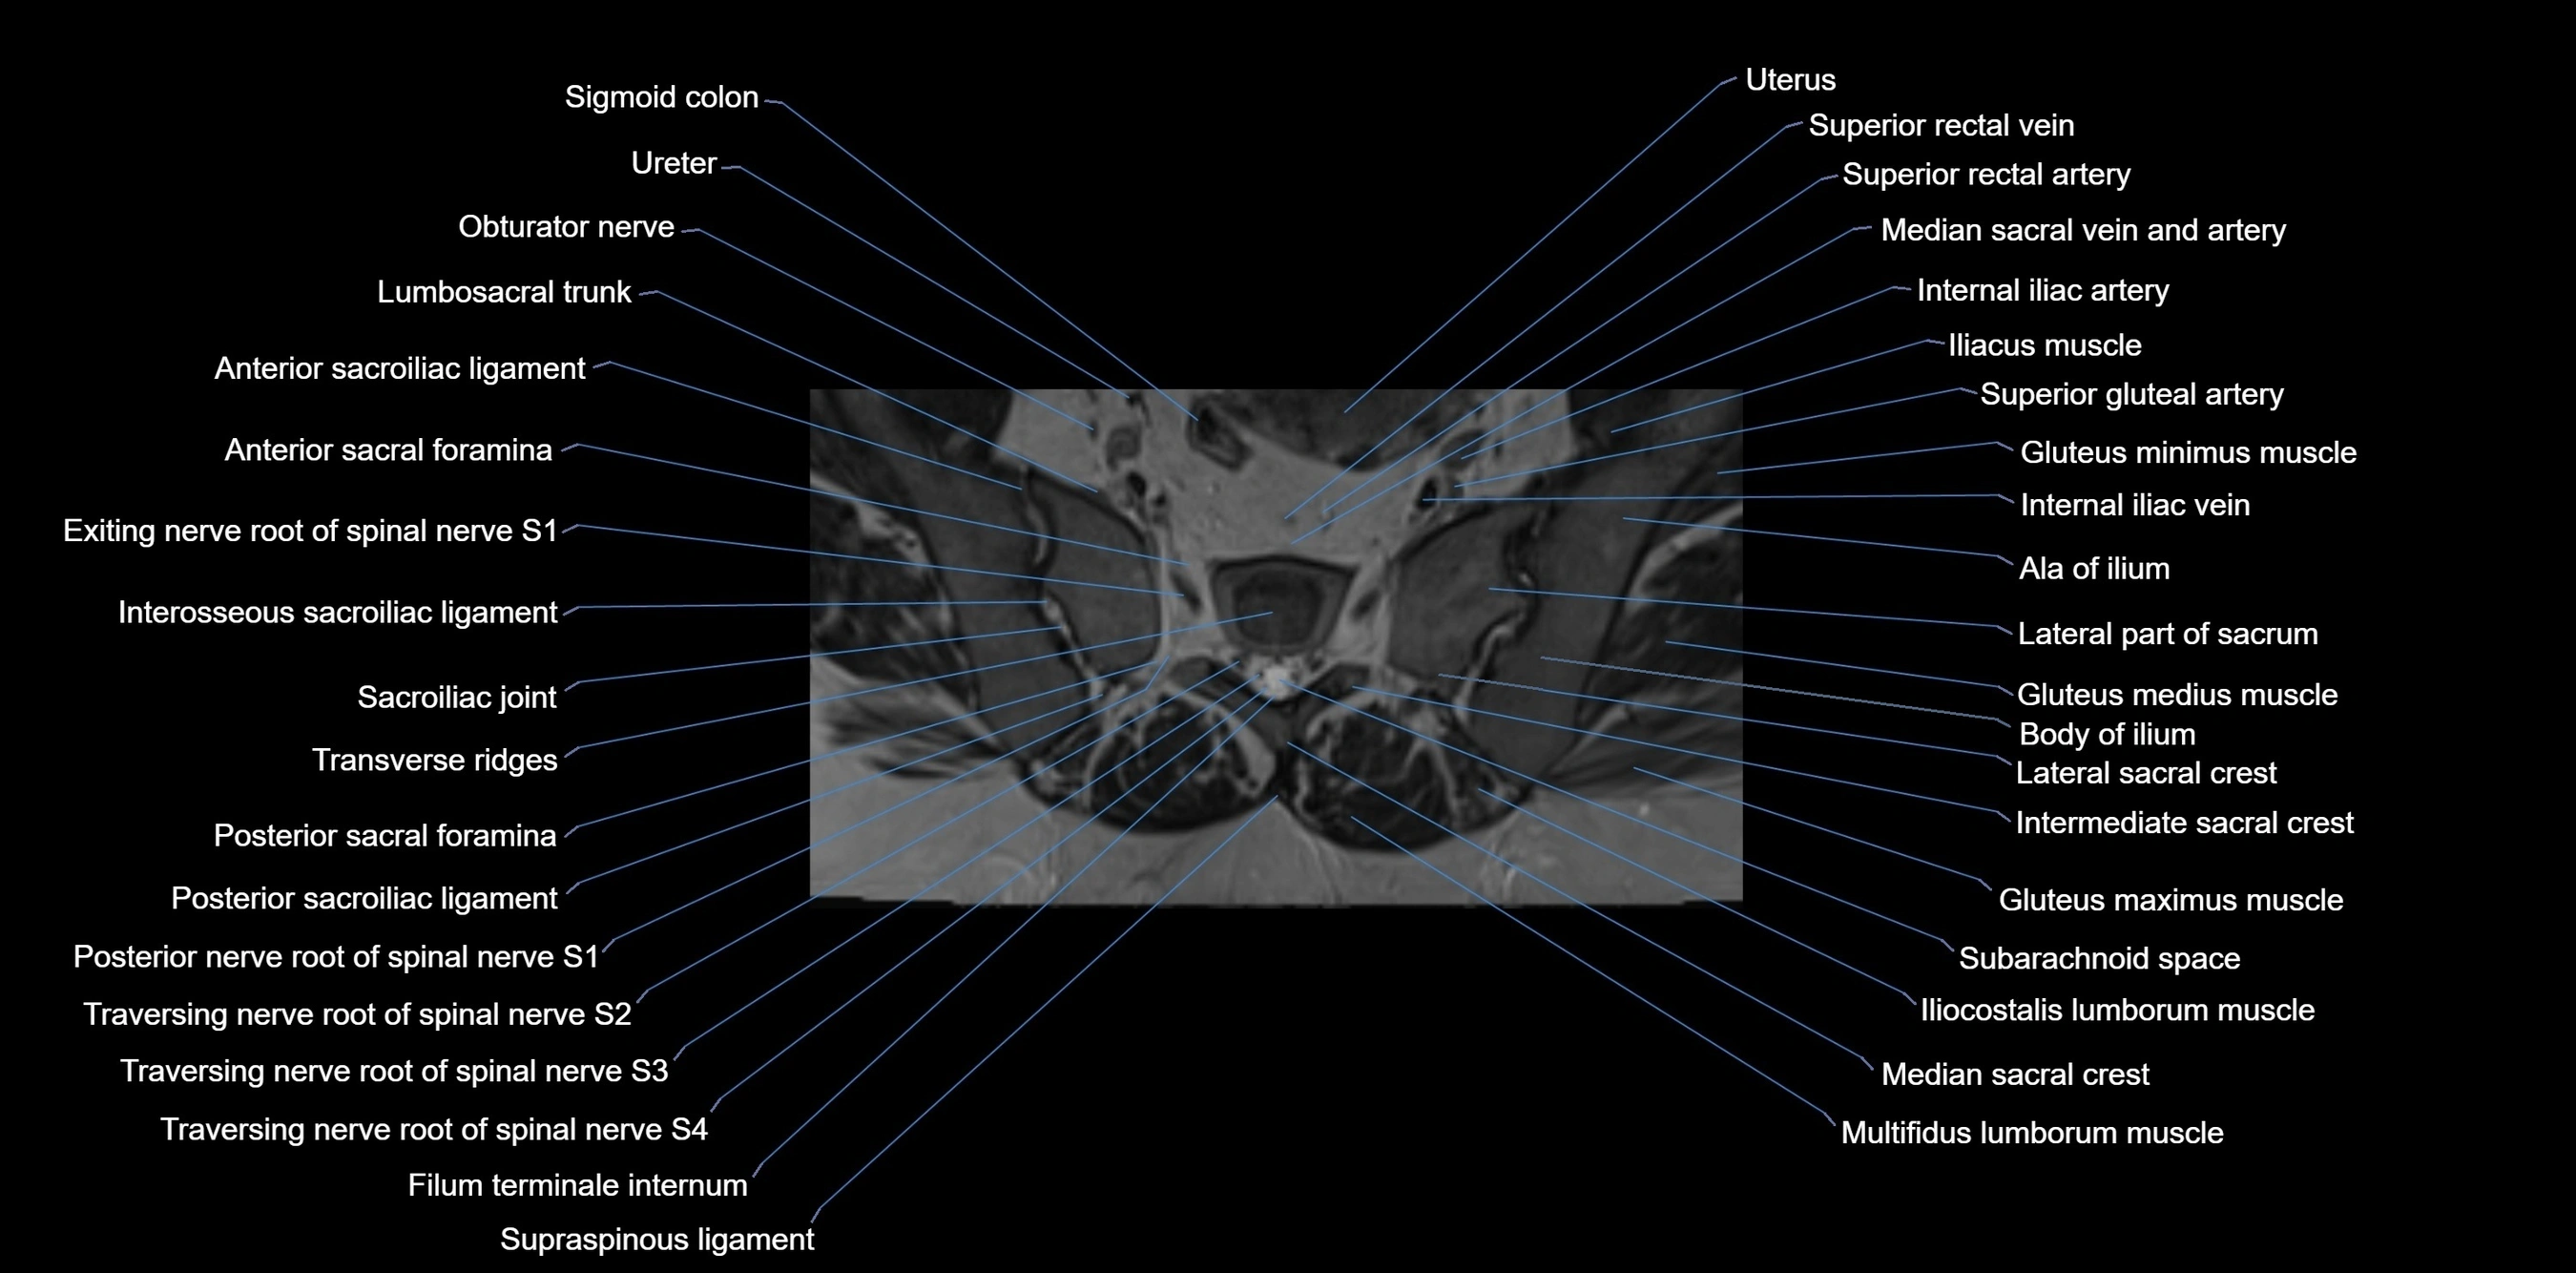

MRI Appearance

T1-weighted images:

• Cortical bone appears very low signal (dark); marrow shows intermediate signal

• Iliac fossa fat is bright against low-signal cortex

T2-weighted images:

• Cortical bone remains dark

• Marrow signal varies depending on fat content; edema or tumor shows hyperintensity

STIR:

• Suppresses fat, making bone marrow edema, fractures, or infiltrative lesions appear bright

• Excellent for trauma, sacroiliitis, and metastatic evaluation

MRI image

image